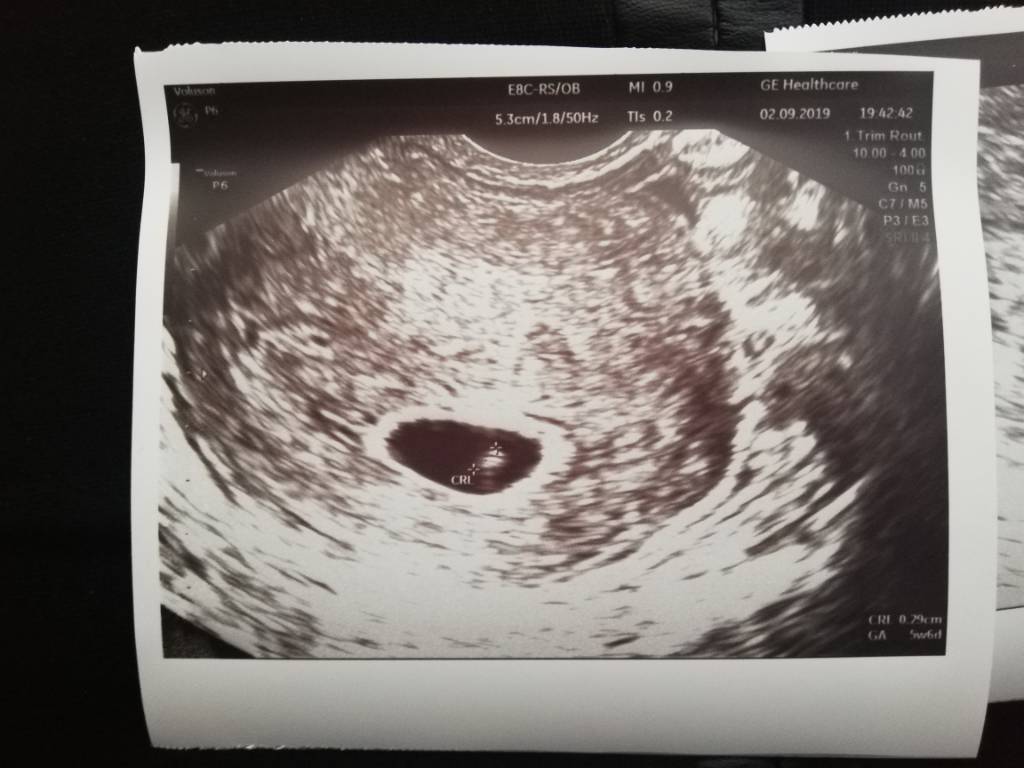

Piękne zdjęcie.Jest kropek i jest serducho [emoji3590]

Wg Om 6t3d wg USG 5t6d ale to nieznacząca różnica.

Z tego wszystkiego nie zapytałam jakie jest tętno [emoji58]Zobacz załącznik 1017577